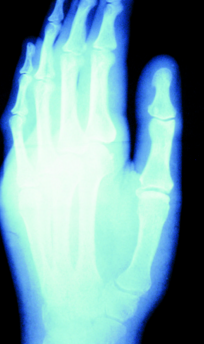

Pharmacotherapy for Neuropathic Pain in the Elderly: Focus on Painful Diabetic Peripheral Neuropathy

Fade Mahmoud, MD; Rajesh R. Tampi, MD, MS, FAPA

Numerous barriers to pain control exist, including patient and physician factors.